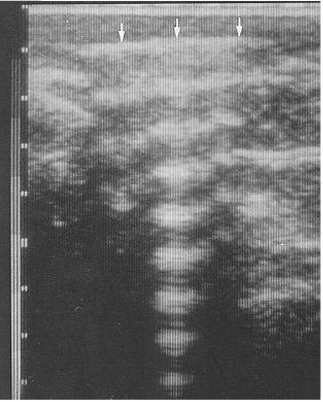

Describe how the reverberation artefact occurs in ultrasonography and how it appears

Ultrasound waves hit objects and reflect back to the scanner head, these waves can then reflect off of the scanner head and then reflect off the tissue again, back to the scanner head. This leads to artefactual whitening in a linear pattern.

<p>What ultrasound artefact is seen here?</p>

What ultrasound artefact is seen here?

Reverberation.